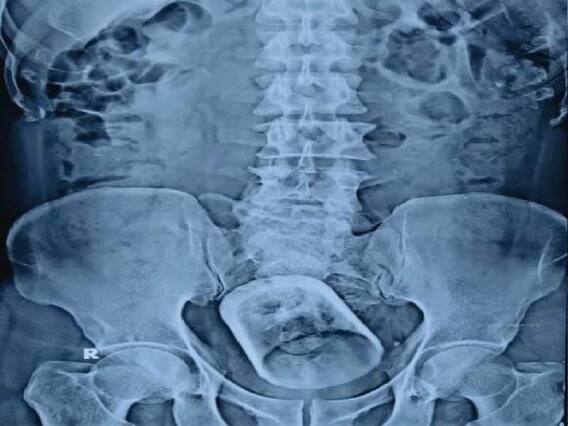

అతడికి సర్జరీ చేసిన డాక్టర్ మక్బూల్ హక్ ఈ కేసుకు సంబంధించి వివరాలు అందించారు. డాక్టర్ మక్బూల్ వద్దకు 55 అయిదేళ్ల వయసుండే వ్యక్తి వచ్చాడు. పొట్టనొప్పి వస్తందనడంతో అల్ట్రాసౌండ్, ఎక్స్ రే తీశారు. అందులో పొట్టలో గ్లాసులాంటి ఆకారం కనిపించింది. అది కూడా పెద్దపేగులో ఇరుక్కున్నట్టు కనిపించింది. ఆ విషయం గురించి రోగిని అడగ్గా టీ తాగుతూ గ్లాసు మింగేశానని చెప్పాడు. అయితే వైద్యుడు ఆ విషయాన్ని నమ్మలేదు. ఎందుకంటే మనిషి ఫుడ్ పైప్ అంత వెడల్పుగా ఉండదు, గ్లాసును మింగడం కుదరదని డాక్టర్ అభిప్రాయం. అందుకే ఆ రోగి నోటి ద్వారా గ్లాసును మింగాడంటే నమ్మశక్యంగా లేదని తెలిపారు. ఆ రోగి కుటుంబసభ్యులను అడిగినా కూడా వారు ఆ గ్లాసు గురించి తెలియదని చెప్పారు.

ఆ గ్లాసును తీసేందుకు ఎండోస్కోపిక్ ప్రక్రియలో పురీషనాళం ద్వారా ప్రయత్నించారు డాక్టర్ మక్బుల్. కానీ అది వీలు పడలేదు. దీంతో పొట్ట కోయక తప్పలేదు. పొత్తి కడుపు ప్రాంతంలో కోసి, పెద్ద పేగును తెరిచి మరీ గ్లాసును తీశారు. రోగి ప్రస్తుతం కోలుకుంటున్నాడు. శస్త్రచికిత్స తరువాత పెద్ద పేగును తిరిగి కుట్టారు. ఈ కుట్టు మానడానికి చాలా సమయం పడుతుందని అంతవరకు జాగ్రత్తగా ఉండాలని సూచించారు వైద్యులు.

ఆ గ్లాసు పొట్టలో ఎలా చేరిందో అంచనా వేసేందుకు వైద్యులు ప్రయత్నించారు. అది నోటి ద్వారా మింగింది కాదని, అసాధ్యమని తేల్చి చెప్పారు. కేవలం మల విసర్జన మార్గం ద్వారానే అది లోపలికి చేరిందని, అసలేం జరిగిందో చెప్పేందుకు రోగి ఇష్టపడడం లేదని వైద్యులు వివరించారు. రోగి ప్రైవసీకి భంగం కలిగించడం ఇష్టం లేకే ఆ విషయాన్ని తెలుసుకునేందుకు ఆసక్తి చూపలదేని తెలిపారు.